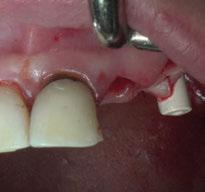

3. Fase quirúrgica final

A los 6 meses de cicatrización, se realizó un nuevo CBCT, obteniendo un nuevo archivo DICOM que alineamos con el STL del encerado. De esta manera, se planificó la posición de los implantes a 4 mm del margen de la restauración final y se diseñó y confeccionó la férula de cirugía guiada dentosoportada en 12-13 y 22-23, la cual imprimimos con la impresora 3D Formlabs®. El provisional

de carga inmediata lo diseñamos con el programa de diseño 3D Exocad® a partir del encerado y se imprimió también en clínica con la misma impresora 3D (Figuras 14-16).

La cirugía se realizó bajo sedación consciente y anestesia local (articaína 4% con epinefrina 40/0,01 mg/ml Ultracain®, 5 carpules en vestibular y palatino de la arcada superior). En primer lugar, se realizaron las exodoncias de los dientes remanentes 11, 21 y 24 y, a continuación, se adaptó la férula de cirugía guiada dentosoportada, insertando los implantes elegidos, en este caso en las posiciones 11 y 21 de Zimvie Tapered Screw-Vent Z3D de 3,7 por 13 mm, 14 Zimvie Tapered Screw-Vent Z3D de 3,7 por 13 mm y 16, 24 y 26 de Zimvie Tapered Screw-Vent Z3D de 4,7 por 13 mm, quedando todos ellos a un torque mayor a 30 Nm. Posteriormente, se realizaron el resto de exodoncias,

produciéndose la fractura de la tabla vestibular del 23, la cual se fijó con un tornillo de osteosíntesis, tras abrir un colgajo mucoperióstico. A continuación, se procedió al relleno de los alveolos que harán de pónticos y los gaps con GEISTLICH BIO-OSS® COLLAGEN 100 mg.

Seguidamente, se colocaron los pilares cónicos TSV-TM de Zimmer® y se atornillaron los pilares provisionales de titanio (Figuras 17-23).